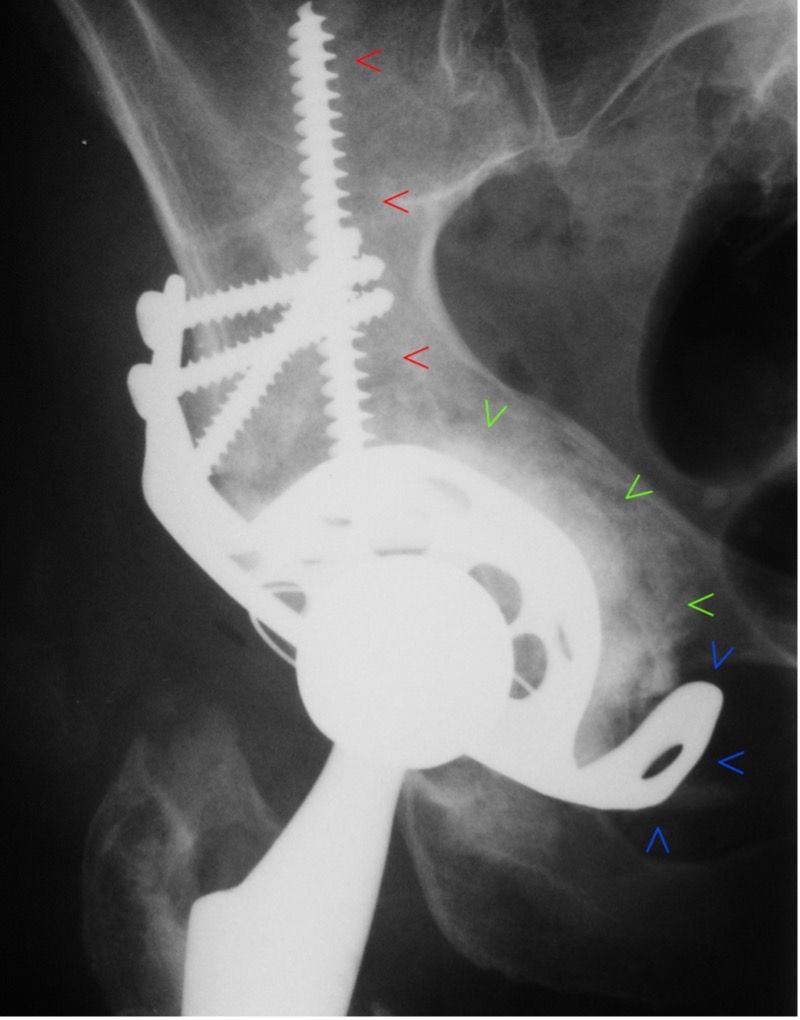

The surgical revision is once more performed in accordance with the therapeutic ADC algorithm [5]. A modular support cup is chosen as a revision system. The large acetabular rim defect is addressed with macroporous titanium augmentation, which exerts a direct transfer of forces onto the remaining bone substance. It is screwed onto the modular revision support cup system having been press-fitted with precision. Bone defects are augmented with biological material using impaction bone grafting outside of the loadbearing areas of the acetabular rim. Half a femoral head is used as a strut-graft analogue to augment the ileum defect. It is important here to separate it from the structural allograft in the load-bearing zone; in the literature this only shows a poor healing rate and high failure rates [11–14]. In this case, however, the main force is transferred onto the healthy bone by the metallic augmentation. The modified strut allograft is only used to seal the impaction bone grafting. Then the construction is fixated with 2 acetabular dome screws with good tension and several dynamic hip screws and flanged screws with a stable angle. The acetabulum itself can only be tensioned in the primary stable implanted modular support cup with adjustable inclination and anteversion.

The postoperative unenhanced X-ray follow-up image now shows a normal implant position with good caudal positioning of the acetabular component compared to the preoperative findings and consecutive anatomical reconstruction of the normal hip rotation centre (Figure 11). The bony acetabular rim defect is bridged by the macrorough augmentation as planned and the caudal hook is positioned in the obdurator foramen.